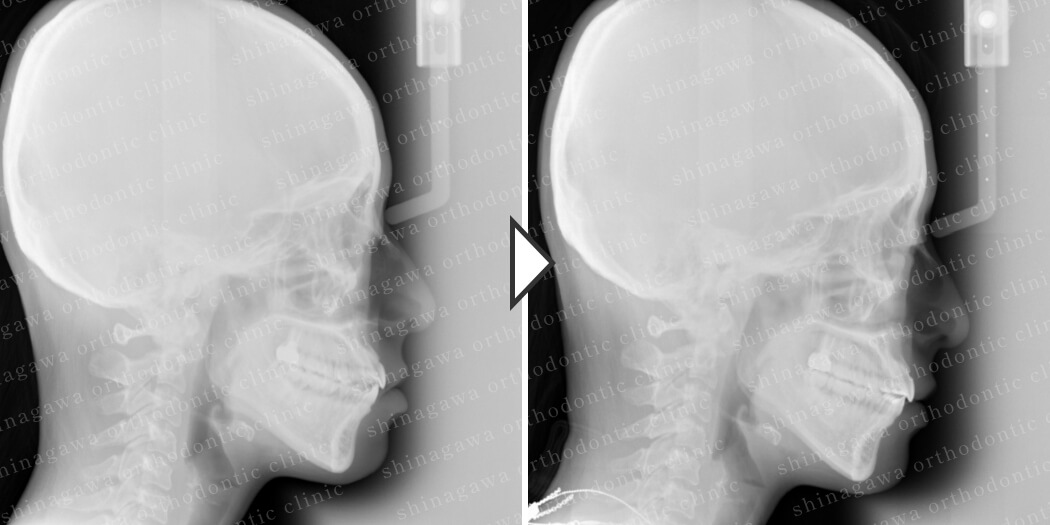

症例7

上下顎前突

| 年齢 | 25 歳 |

|---|---|

| 性別 | 女性 |

| 住所 | 神奈川県川崎市 |

| 主訴 | 出っ歯 |

| 不正咬合の種類(診断) | 上下顎前突 |

| 装置 | リンガル |

| 抜歯/非抜歯 | UR4, UL4, LR4, LL4 |

| 期間 | 32M |

| 費用 | 1,430,000 円 |

| リスク・副作用 | 矯正治療による歯の移動に伴う痛み, 虫歯, 歯肉退縮, 歯根吸収 |